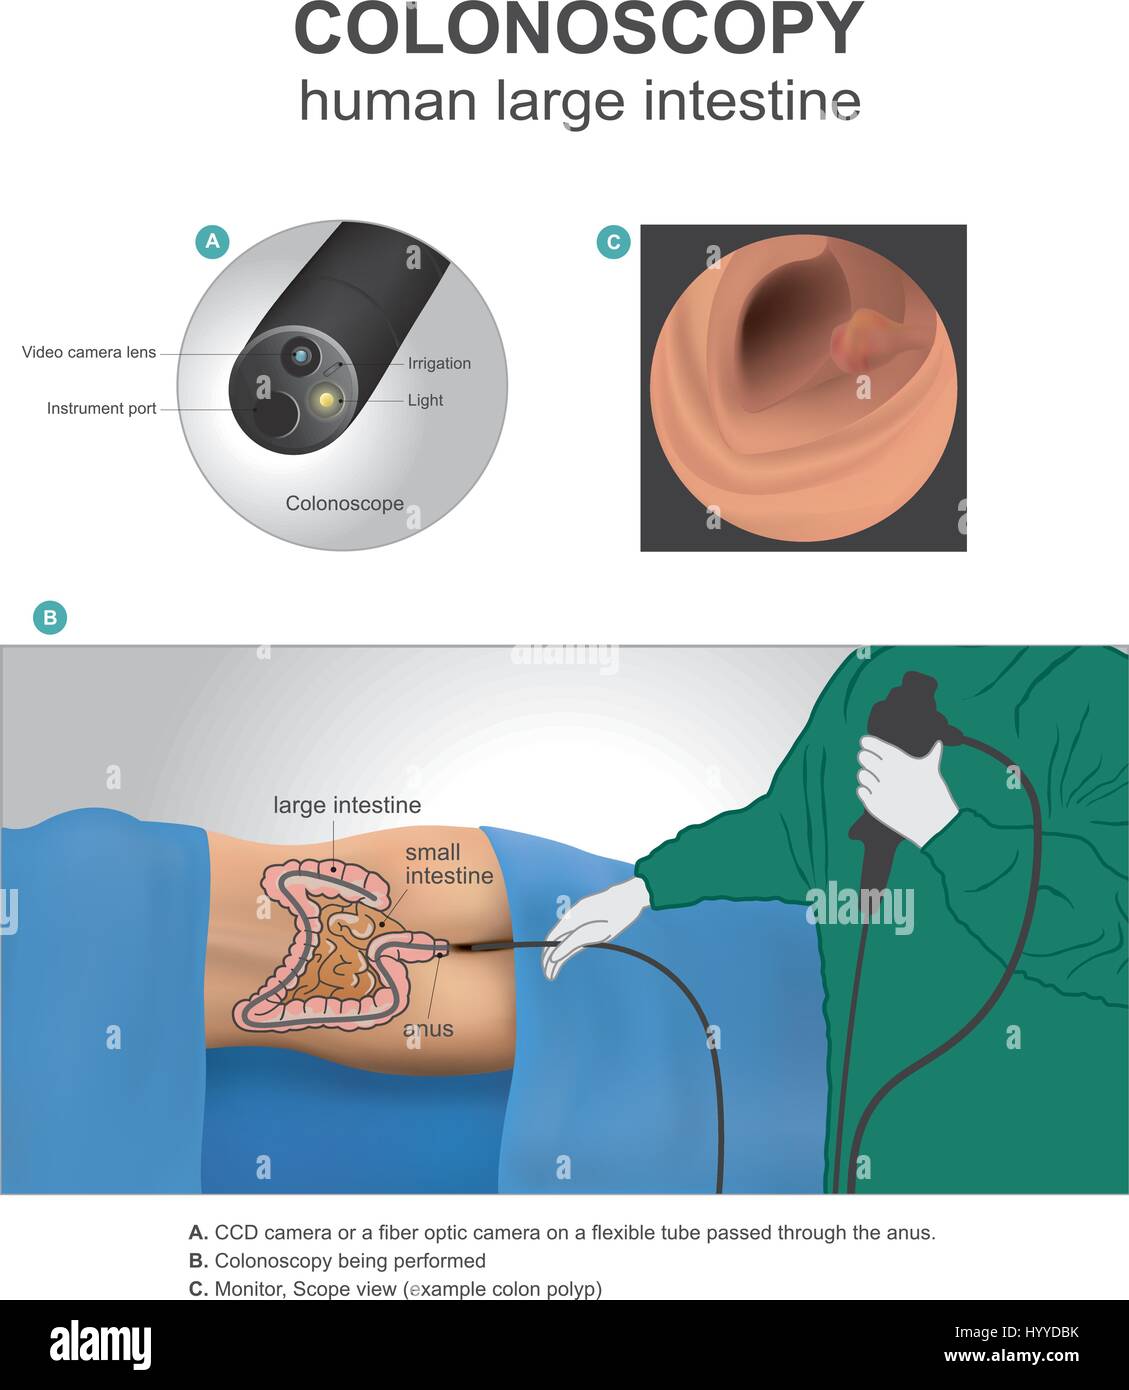

La colonscopia è un test che permette al medico di guardare la fodera interna del vostro intestino crasso. Anatomia umana illustrazione, arte vettoriale. Illustrazione Vettorialehttps://www.alamy.it/image-license-details/?v=1https://www.alamy.it/foto-immagine-la-colonscopia-e-un-test-che-permette-al-medico-di-guardare-la-fodera-interna-del-vostro-intestino-crasso-anatomia-umana-illustrazione-arte-vettoriale-137671511.html

La colonscopia è un test che permette al medico di guardare la fodera interna del vostro intestino crasso. Anatomia umana illustrazione, arte vettoriale. Illustrazione Vettorialehttps://www.alamy.it/image-license-details/?v=1https://www.alamy.it/foto-immagine-la-colonscopia-e-un-test-che-permette-al-medico-di-guardare-la-fodera-interna-del-vostro-intestino-crasso-anatomia-umana-illustrazione-arte-vettoriale-137671511.htmlRFHYYDBK–La colonscopia è un test che permette al medico di guardare la fodera interna del vostro intestino crasso. Anatomia umana illustrazione, arte vettoriale.